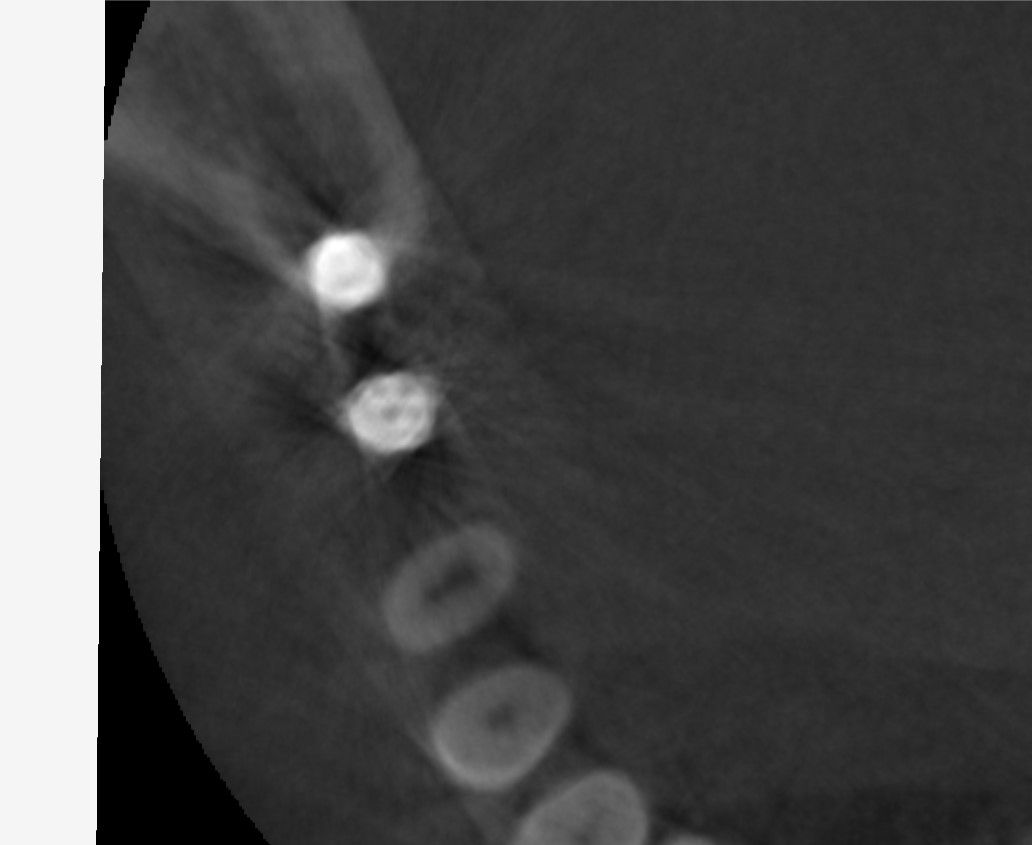

先日インプラントの型取をした患者さんの被せ物が出来上がってきました。

これをネジを使ってインプラントに接続します。